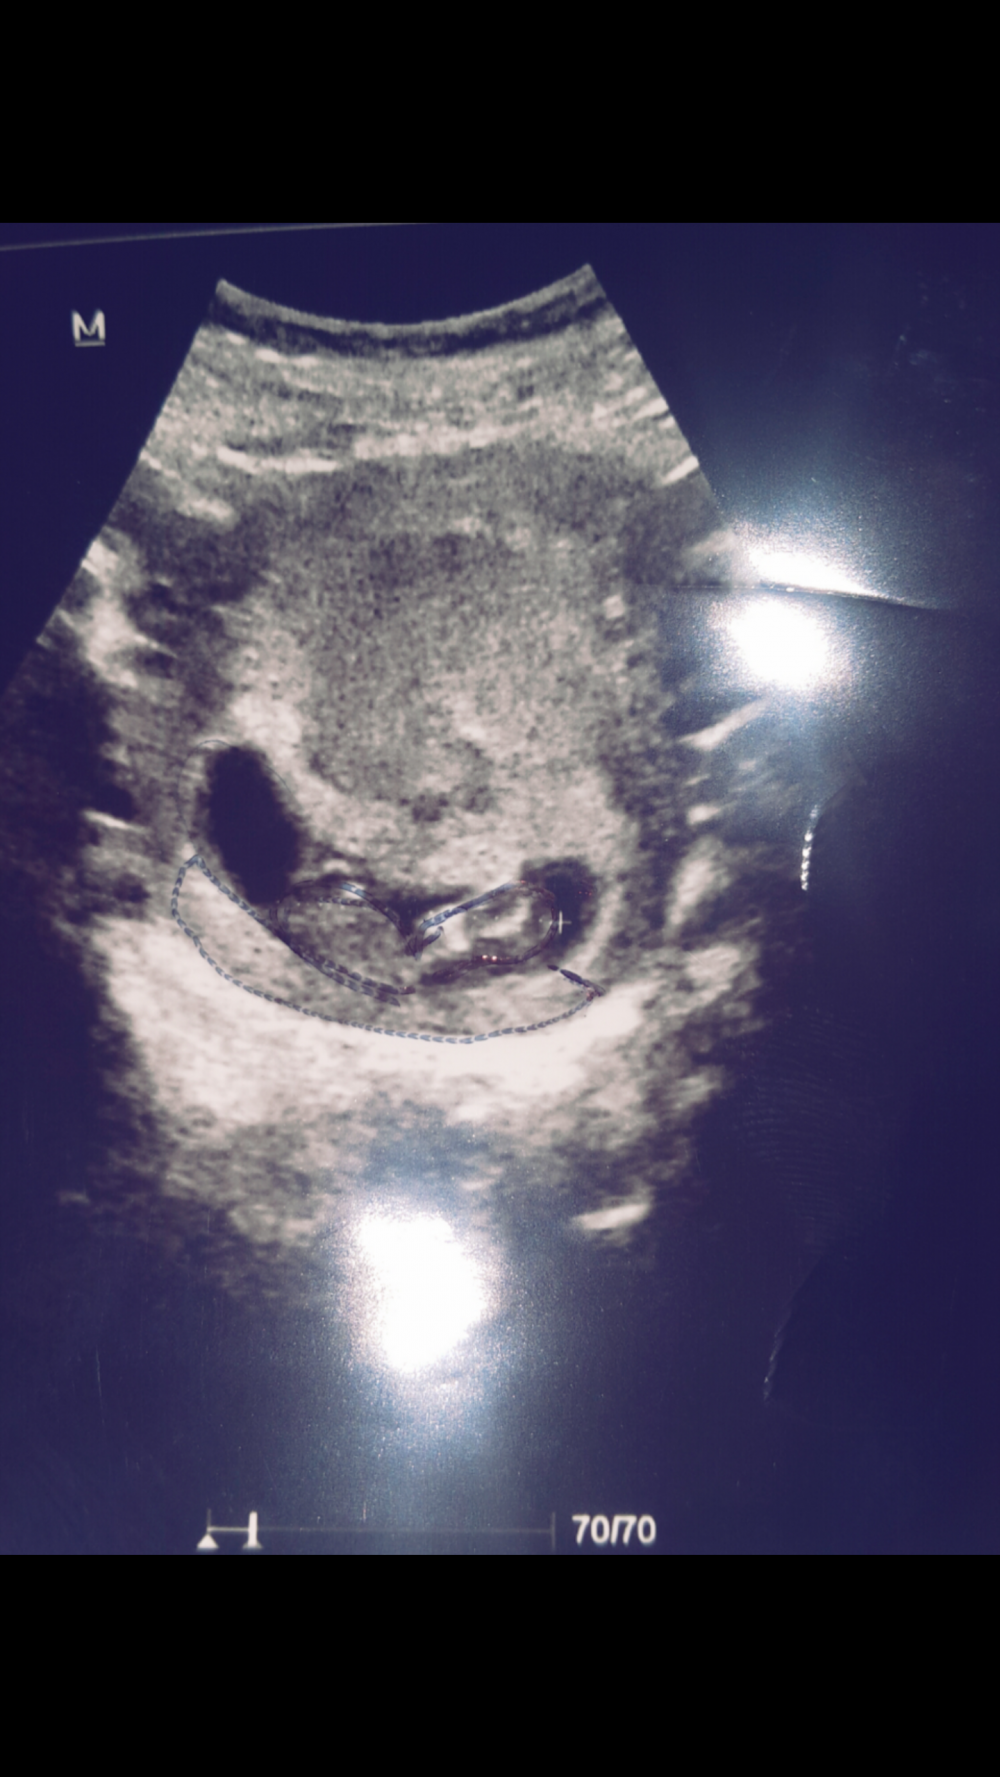

لا سوي لقط لشاشه اللي هي لصوره بعدين نزليها وتنزل

احيرا الحمدلله نزللللللت بعد معاناة